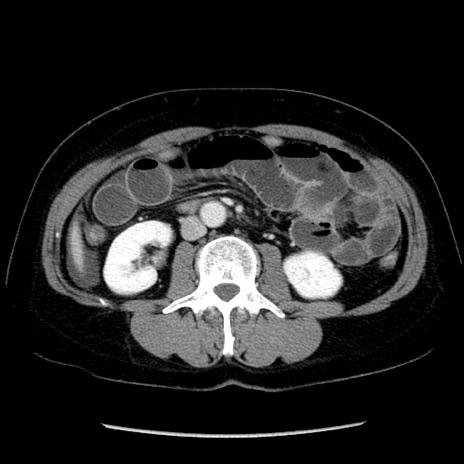

矢状断像